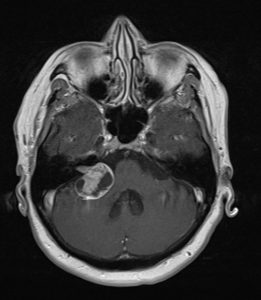

Ασθενής γυναίκα 68 ετών με προοδευτική επιδείνωση της ακοής δεξιά και επεισόδια ιλίγγων και διαταραχής της ισορροπίας και βάδισης.

Η μαγνητική τομογραφία εγκεφάλου ανέδειξε χωροκατακτητική εξεργασία στη δεξιά γεφυροπαρεγκεφαλιδική γωνία συμβατή με ακουστικό νευρίνωμα (αιθουσαίο σβάννωμα) και πίεση επί του στελέχους (Koos IV).

Η ασθενής υπεβλήθη σε δεξιά οπισθοσιγμοειδική κρανιοτομία και ολική αφαίρεση της βλάβης.